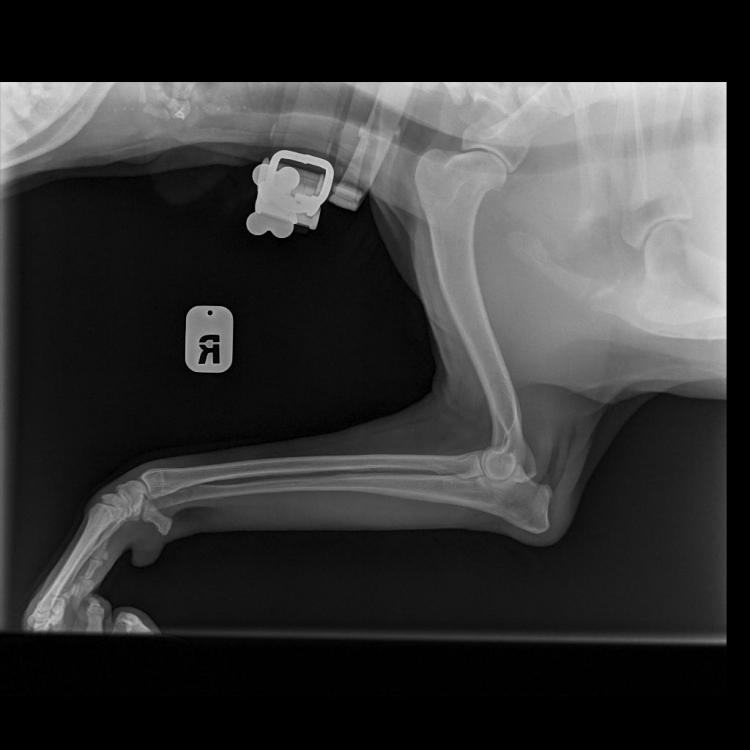

Яся&Лина&Лора Опубликовано 4 июня, 2020 Опубликовано 4 июня, 2020 Теперь все по порядку. Друзья, спасибо за терпение и выдержку! Писала на бегу. И, конечно же, спасибо за поддержку! В общем, Никуня нас немножко сегодня испугала, если честно. Поэтому побежали не раздумывая, выяснять что случилось с лапой. Как понимаете, боишься уже всего! В клинике нас встретил давно знакомый и совсем не страшный доктор Климухин И.Н. Очень внимательно и долго нас осматривал и щупал. Потом уже в конце приема сказал, что Никуся невероятно терпеливая девочка, молчит и терпит до последнего, даже никаких звуков не издаёт. Потом мы сделали 3 рентгеновских снимка и сдали кровь: общий и б/х (для контроля перед назначением обезболивающих). Кровь сдавали и температуру мерили с настоящим голдячим достоинством! Ну, правда... немножко случилась экспресс-линька.... Мне кажется, в Нике осталась вся клиника! Доктор нам отзвонился по анализам очень быстро. Анализы у нас прекрасные! Ура! За исключением повышенных лейкоцитов. Поэтому нужен контроль на фоне лечения через несколько дней. По рентгену криминала тоже нет никакого. По результату осмотра, есть небольшие проблемки с суставами, но ничего критичного. При этом, однозначно есть хромота на правую лапку, а реагирует при осмотре и левая тоже. Предположили, что, возможно, Никуся неудачно кувырнулась дома или оступилась?! Последнее время дожди и мы никуда не выезжали. Дома Никуся на диван залазит крайне редко. Внизу травмироваться вроде как негде?! Гуляет она всегда с огромным удовольствием. Возможно, на улице неудачно рванула вперед. Но, слава Богу! Ничего не порвала! И не вывихнула! В итоге доктор нам назначил Превикокс на 5 дней. В воскресенье ждет нас на контрольный осмотр, чтоб оценить динамику и надо будет повторить общий анализ крови, посмотреть лейкоциты. Счастью не было предела, волшебное слово «домой»! За все страдания получила немного вкуснях. «Где тут вкусняхи дают?» «Ням ням» «А мы уже домой?! Правда?!» «Тогда можно и расслабится!» «Поехали уже! Че стоим?!» 7